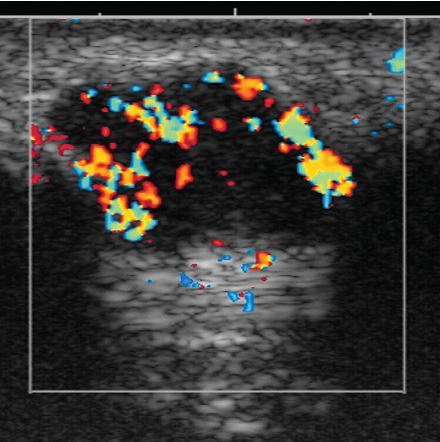

• central dot sign = cystic lesions with central solid components containing blood flow

• complications

• biliary stones

• bild duct obstruction

• cholangitis

• liver abscess

• hepatic fibrosis –> portal hypertension

• cholangiocarcinoma

• the kidneys may also be affected with a variety of cystic diseases